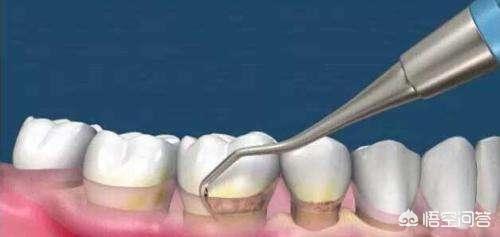

Causes:1) Accumulation bactérienne, où les métabolites bactériens adhèrent à la surface de la dent et ne peuvent être éliminés par un brossage normal. 2) . Tartre dentaire Le tartre dentaire désigne la plaque minéralisée déposée à la surface de la dent, qui se divise en deux types, le tartre supra-gingival et le tartre sous-gingival, en fonction de son site de dépôt et de sa nature. (1) Le tartre supra-gingival est situé sur la surface de la dent au-dessus de la marge gingivale et peut être vu directement à l'œil nu. (2) Le tartre sous-gingival est situé sur les surfaces des racines sous la marge gingivale, dans les poches gingivales ou les poches parodontales, où il ne peut pas être vu directement à l'œil nu et est plus susceptible de conduire à une parodontite.3). Occlusion traumatique Pendant l'occlusion, si la force occlusale est trop importante ou si elle est exercée dans une direction anormale, elle dépasse la force combinée que les tissus parodontaux peuvent supporter, ce qui entraîne une occlusion qui endommage les tissus parodontaux ; on parle alors d'occlusion traumatique. L'occlusion traumatique comprend le contact précoce pendant l'occlusion, l'interférence avec la dentition et le grincement nocturne des dents. 4). Les impactions alimentaires contribuent également à l'inflammation des tissus parodontaux. La parodontite entraîne souvent le déchaussement d'une ou de plusieurs séries de dents.

Traitement : si le déchaussement est inférieur à 2 mm, procéder à un nettoyage supra-gingival ou à un grattage sous-gingival, ajuster l'occlusion, éliminer les impactions alimentaires, utiliser des antibiotiques, inciser et drainer l'abcès, etc. ; si le déchaussement est supérieur à 2 mm, il est recommandé d'extraire, et une forte rétention détruira l'os alvéolaire avoisinant.

Nettoyage régulier de la bouche, grattage sous-gingival et surfaçage radiculaire si nécessaire, et chirurgie du lambeau parodontal en cas de parodontite sévère. Seul un traitement actif permet de ralentir efficacement la progression de la maladie parodontale.

Si les dents sont déchaussées en raison d'une parodontite, cela se manifeste par la présence de beaucoup de tartre, de triangles noirs dus à la récession gingivale et de saignements des gencives. Pour effectuer un traitement parodontal, la méthode la plus élémentaire est le nettoyage aux ultrasons, le grattage sous-gingival pour enlever les dents autour du tartre, de la plaque et d'autres éléments qui provoquent l'inflammation. En plus d'un auto-nettoyage soigneux des dents (veillez à utiliser du fil dentaire chaque fois que vous vous brossez les dents), vous devrez également effectuer des contrôles réguliers. Si les lésions tardent à se résorber, vous pourrez bénéficier d'un traitement chirurgical parodontal en fonction de la situation, le but principal de ce traitement étant d'éliminer complètement l'inflammation autour des dents et de favoriser la cicatrisation.